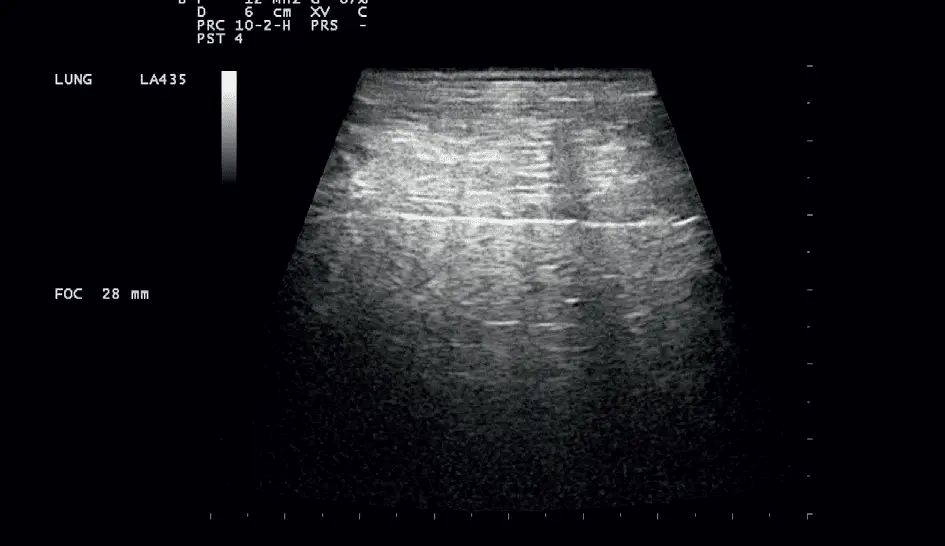

W badaniu USG płuc w siódmej przestrzeni międzyżebrowej w linii przymostkowej lewej był widoczny obszar dużej konsolidacji płuc (do 7 cm głębokości) z bronchogramem powietrznym dynamicznym przechodzącym miejscami w statyczny z widocznymi pułapkami powietrznymi. Obszar konsolidacji był otoczony obszarem zlewających się zespołów śródmiąższowo-pęcherzykowych i pęcherzykowych. Obraz USG wskazywał na zapalenie płuc, najprawdopodobniej na tle zachłyśnięcia (zdj. 2). Została wskazana antybiotykoterapia o szerokim spektrum (bakterie G-dodatnie, G-ujemne i beztlenowce) przez minimum 4–6 tygodni. Poproszono o wykonanie kontrolnego RTG klatki piersiowej po 3–4 tygodniach leczenia. Pacjent otrzymał metronidazol i enrofloksacynę i po 19 dniach pojawił się na kontrolę z nieustającym kaszlem i odkrztuszeniem.

Wykonano ponownie badanie klinicznie, w którym stwierdzono brak trzeszczeń nad polami płucnymi, ogniskowo lewostronnie zaostrzony szmer oskrzelowy w dolnych polach płucnych. Wykonano kontrolne badanie USG płuc, w którym stwierdzono w siódmej przestrzeni międzyżebrowej lewostronnie w linii przymostkowej widoczny opisywany wcześniej obszar konsolidacji, o wyraźnie mniejszym zakresie, częściowo ukryty pod żebrem, bez widocznego bronchogramu powietrznego. Obraz wskazywał na proces gojenia z możliwym częściowym zwątrobieniem płuca (zdj. 3). Antybiotykoterapia została utrzymana, a dodatkowo dodano syrop Pectodrill 2 razy dziennie po 5 ml przez 7 dni.